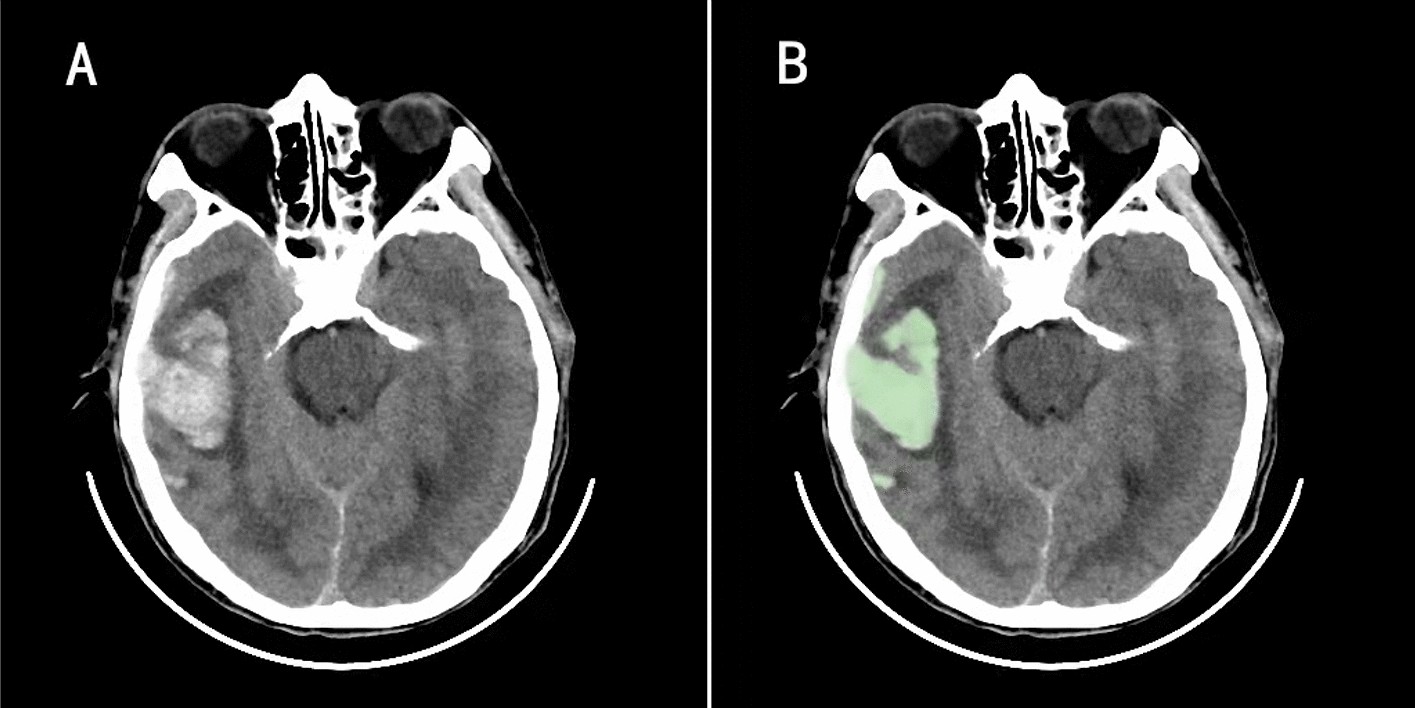

Figure 2

On the 3D slicer software, the contusion volume is provided by manually selecting the region of interest, setting the threshold based on the Hounsfield unit (the fixed thresholds of 110 and 50 HU) to distinguish the contusion part from the surrounding normal brain tissue, and automatically summarizing the adjacent voxels (A and B).